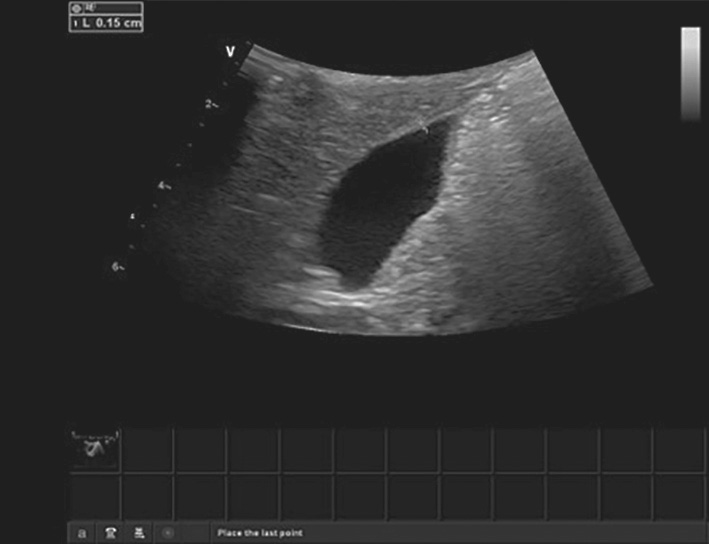

图2-1-5 胆囊长径测量

当胆囊出现褶皱时,测量两个径线后相加